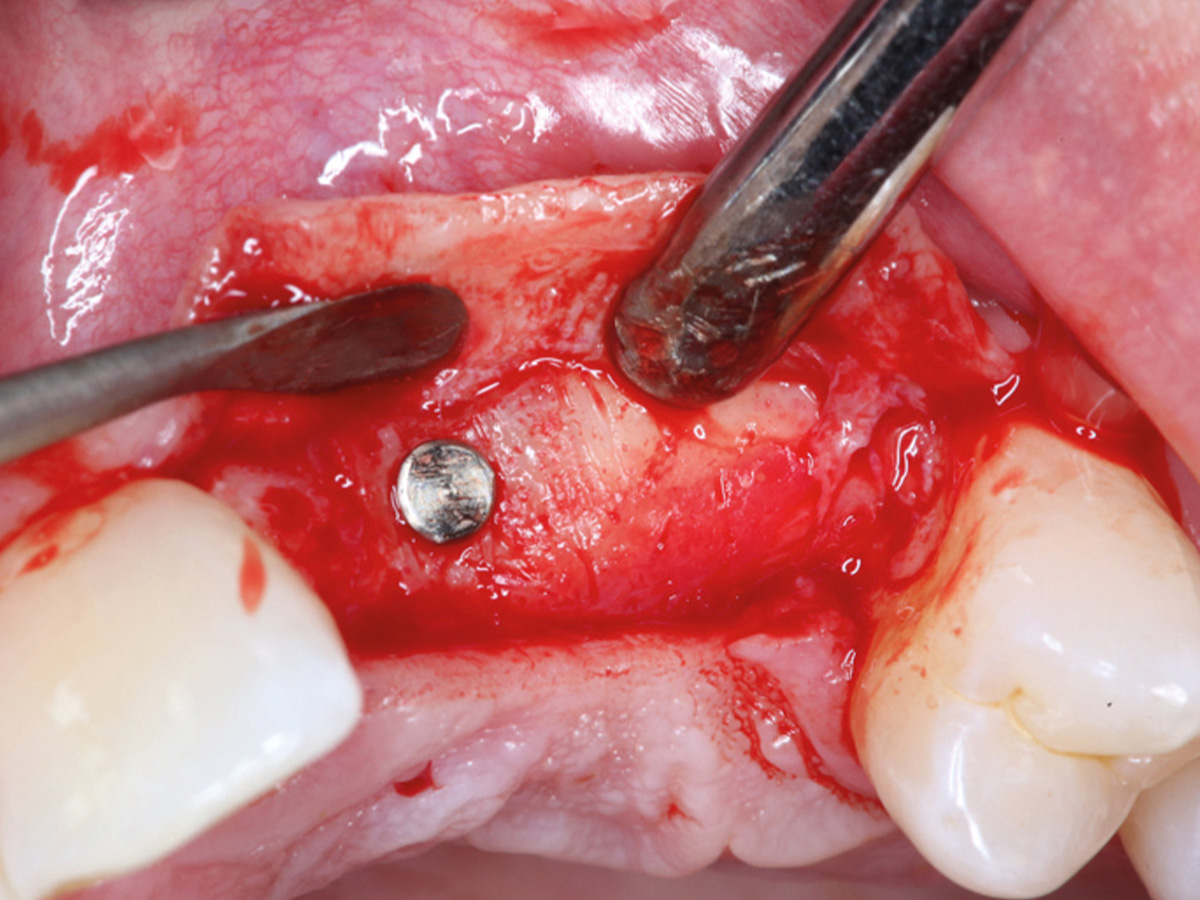

Abbildung 1

Klinische Ausgangssituation lateral, spontane Blutung.